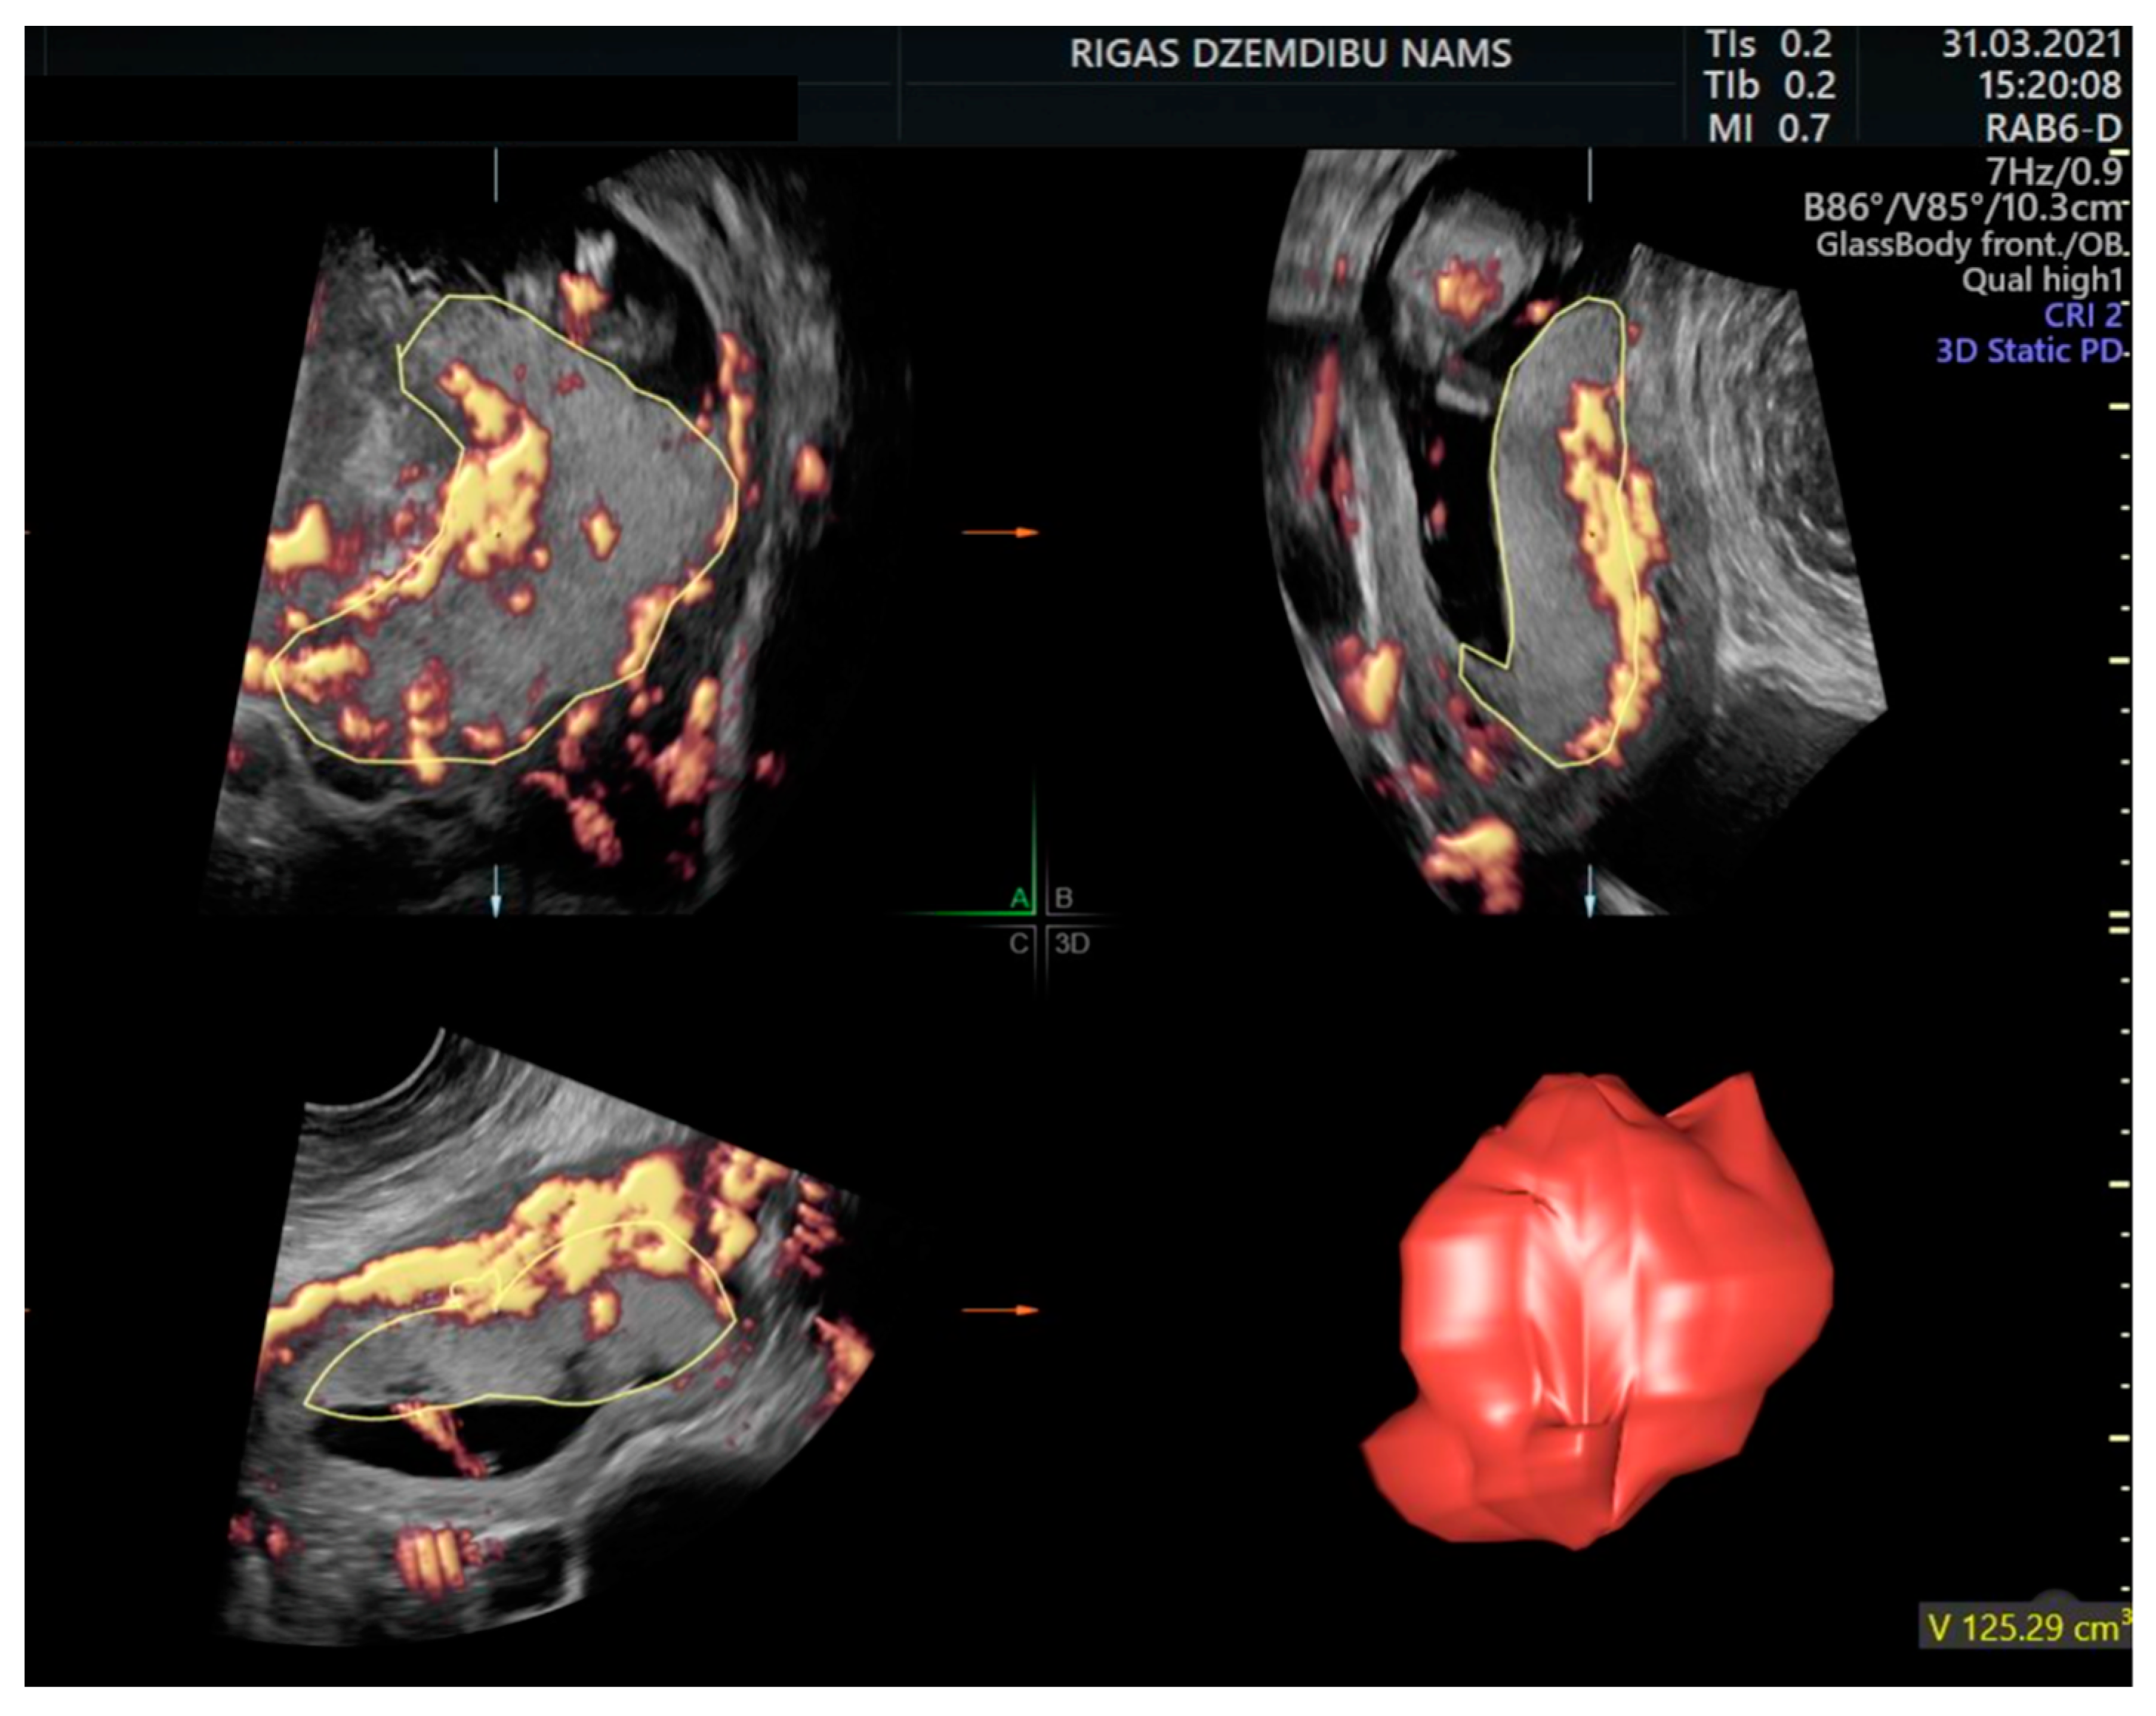

2. Materials and Methods